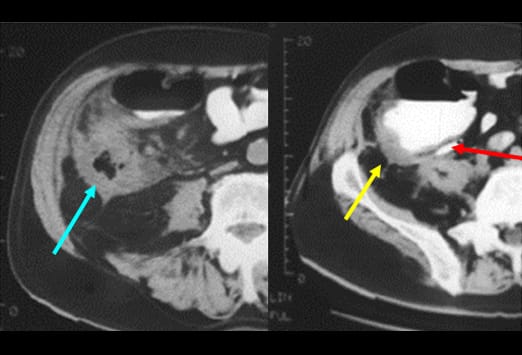

Diese Abbildung zeigt einen Appendikolithen (weißer Pfeil) mit einem großen Abszess (blau gestrichelte Linie), der einzelne Lufteinschlüsse enthält (roter Pfeil). Es zeigen sich angrenzend weitere entzündliche Veränderungen im Bereich des terminalen Ileums (gelber Pfeil). Eine Perforation stellt die schwerste Form der fortgeschrittenen Appendizitis dar, da es hier zu einer Infektion der Bauchhöhle kommt. Eine Perforation kann somit einen Abszess, eine Peritonitis und einer Sepsis zu Folge haben.